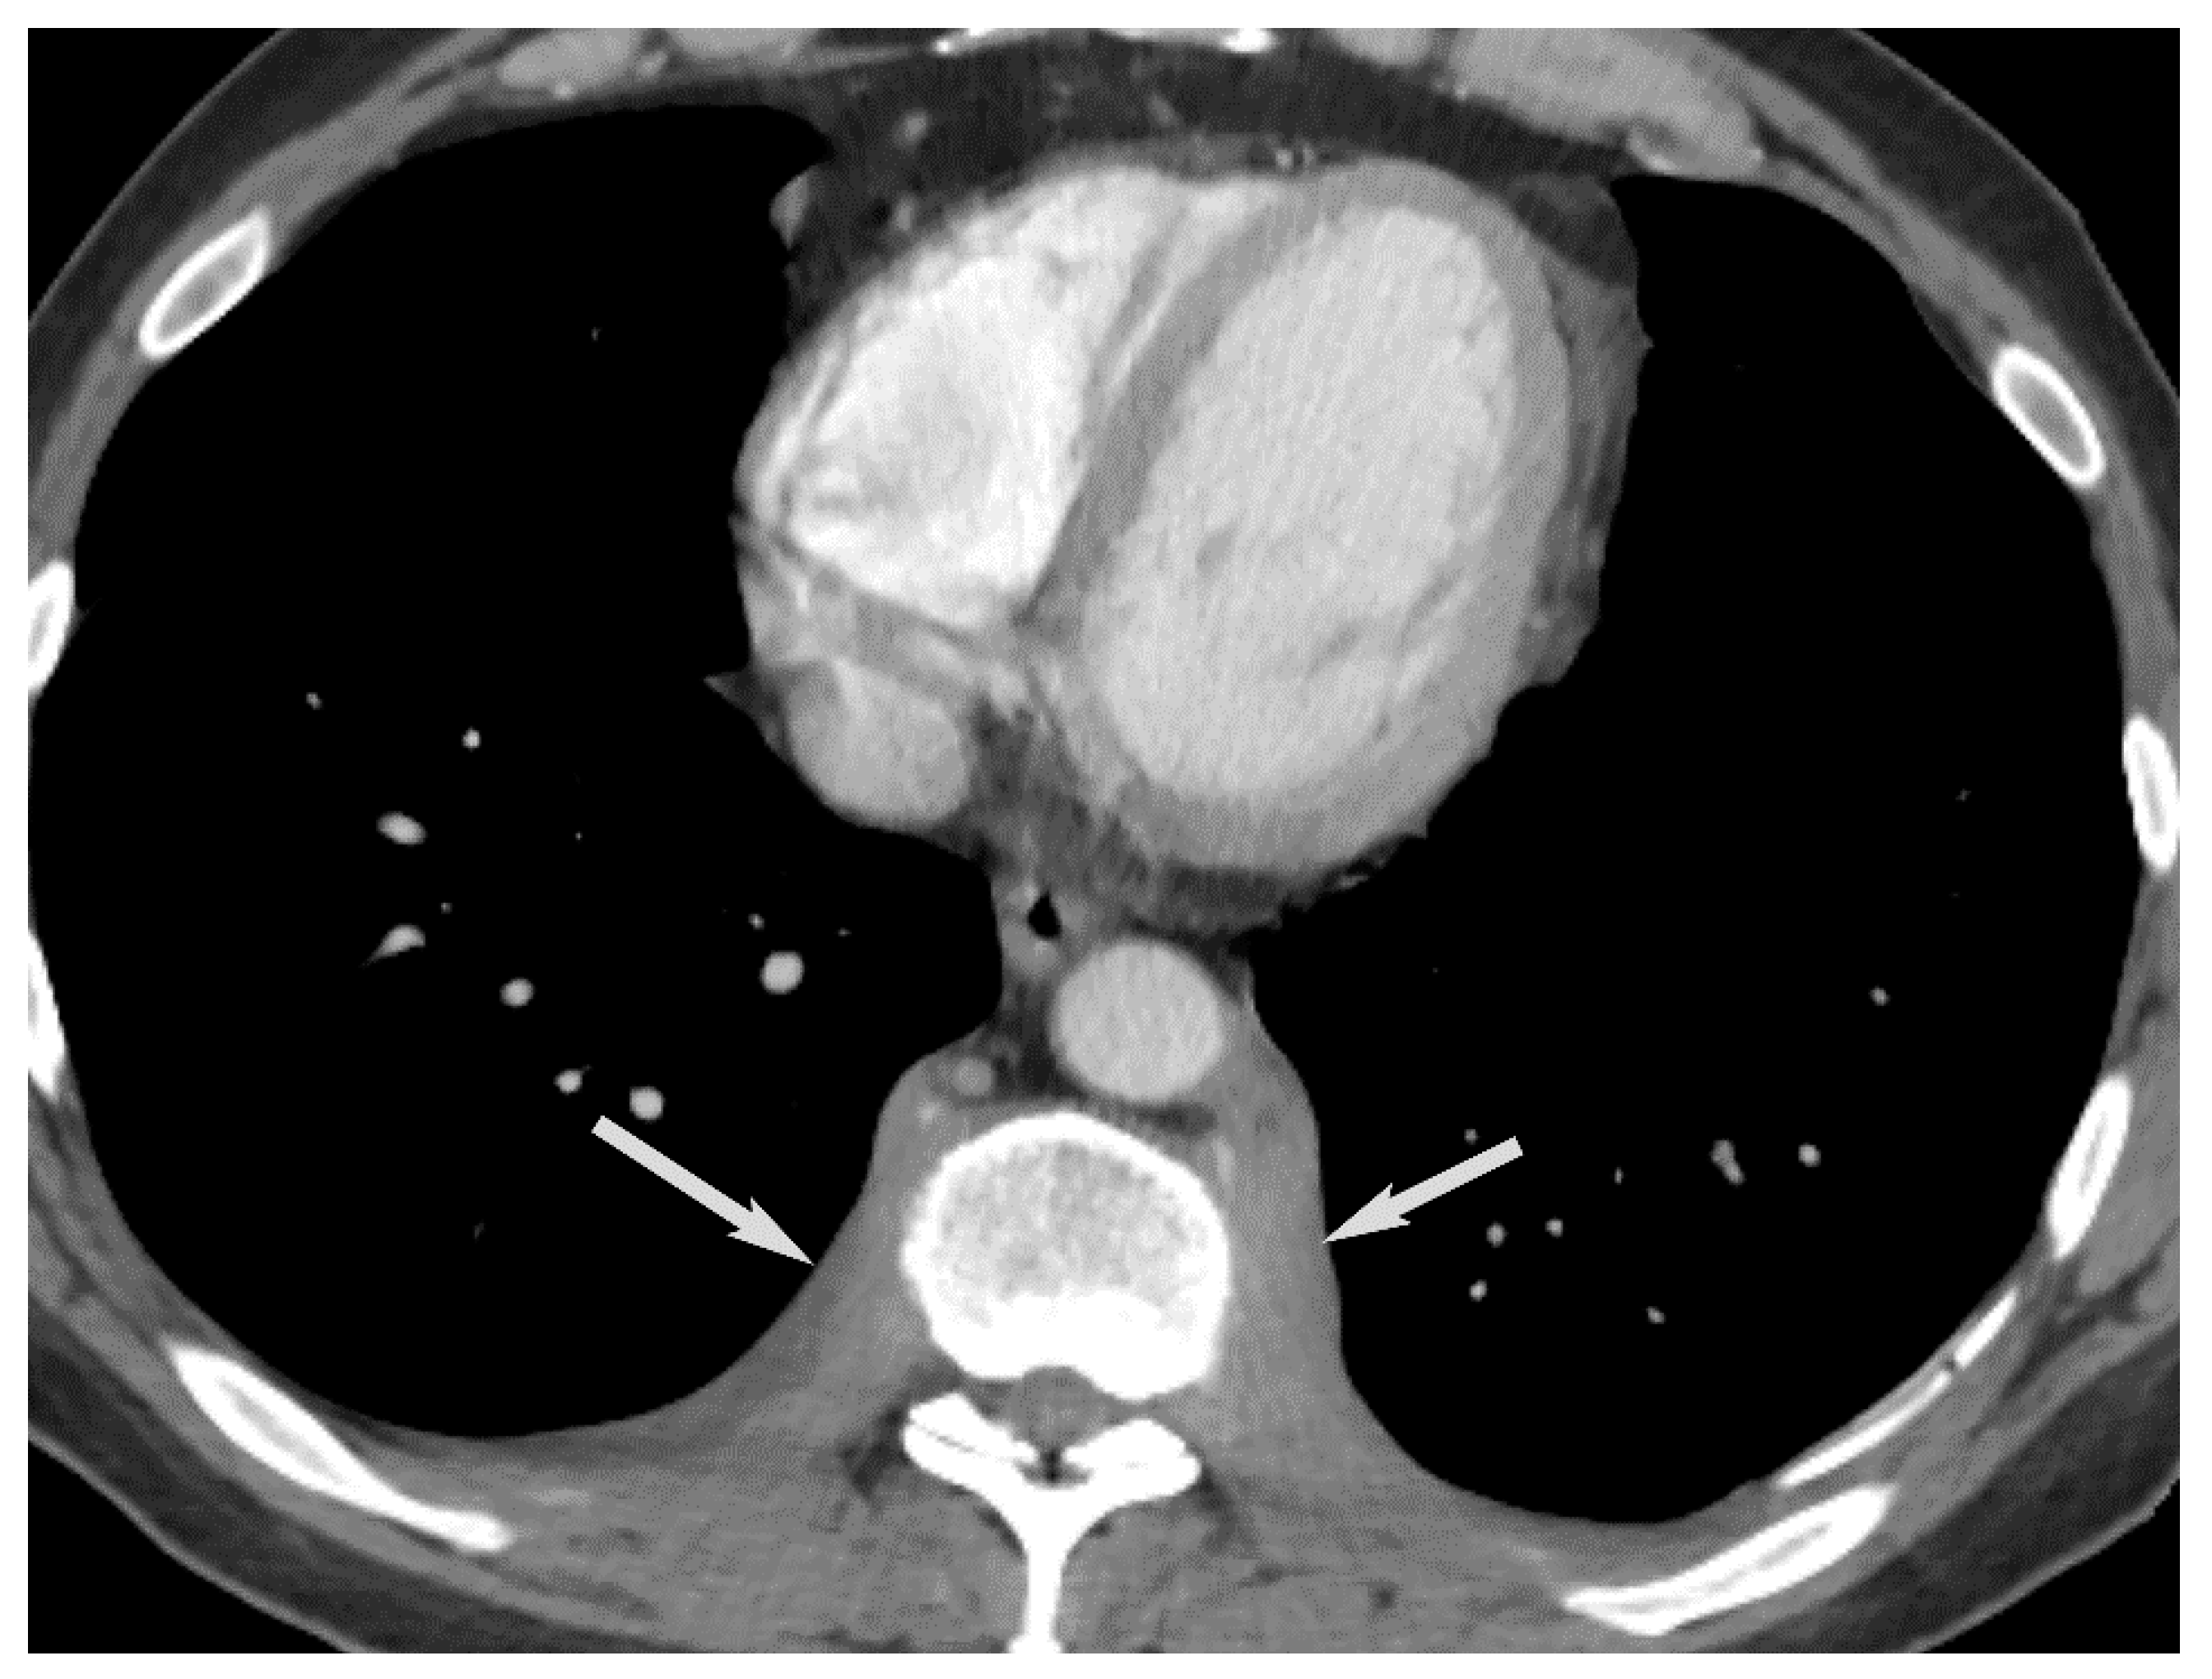

7. Germ Cell Tumors

9. Hypervascular Lesions